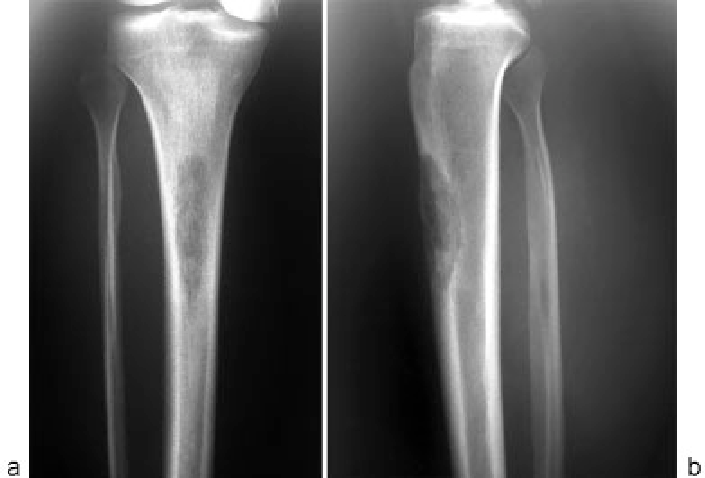

- Дисплазия мыщелков бедренной кости. Это означает, что межмыщелковый желоб, по которому скользит надколенник, слишком мелкий или плоский. У коленной чашечки просто нет достаточно глубокой «колеи», чтобы удерживаться на месте.

- Рентгенография. Это базовое исследование. Снимки делаются в нескольких проекциях, чтобы оценить положение надколенника, форму межмыщелкового желоба и исключить костные повреждения.